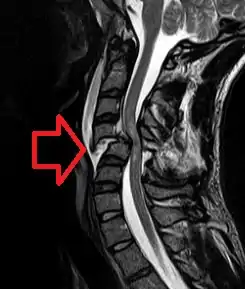

| MRI of fractured and dislocated neck vertebra that is compressing the spinal cord | |